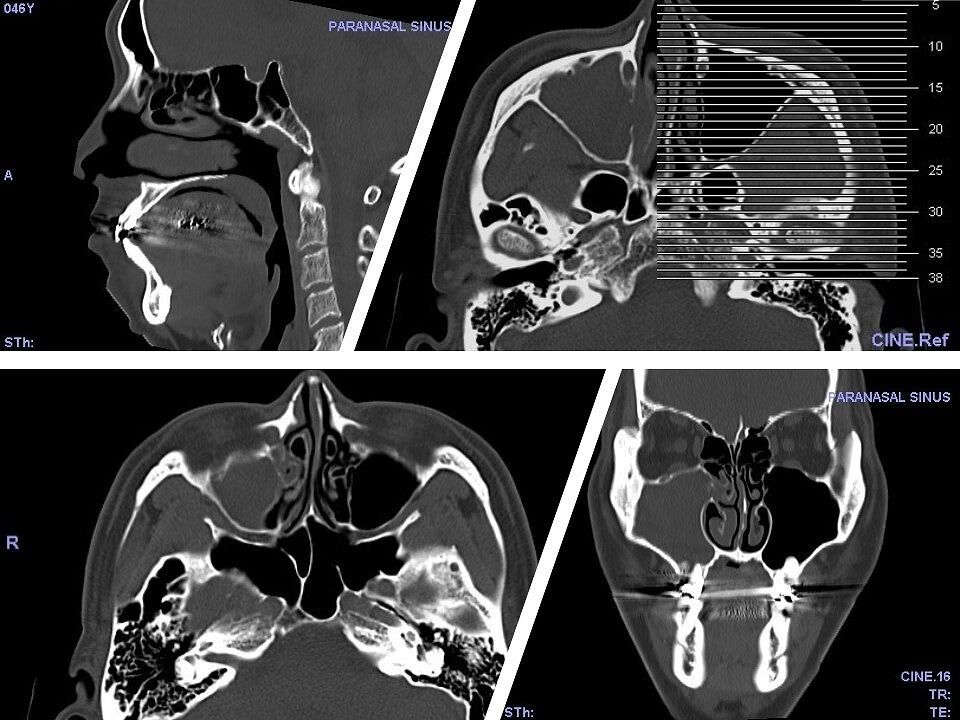

人生初CT記念!

なんかCTって凄いね・・・。